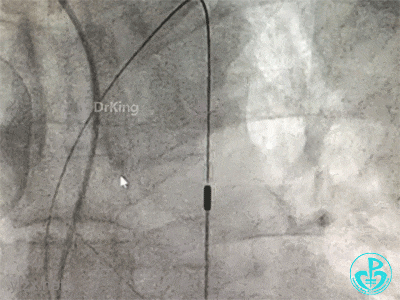

更换指引导管,导丝分别进入前降支和回旋支,球囊分别扩张前降支开口和回旋支开口,IVUS确认左主干及分支开口病变,前降支中段植入支架,对角支开口球囊扩张。

左主干分叉病变采取Crush双支架术式,回旋支开口植入支架,前降支开口球囊挤压后左主干到前降支植入支架(Crush双支架术式)。